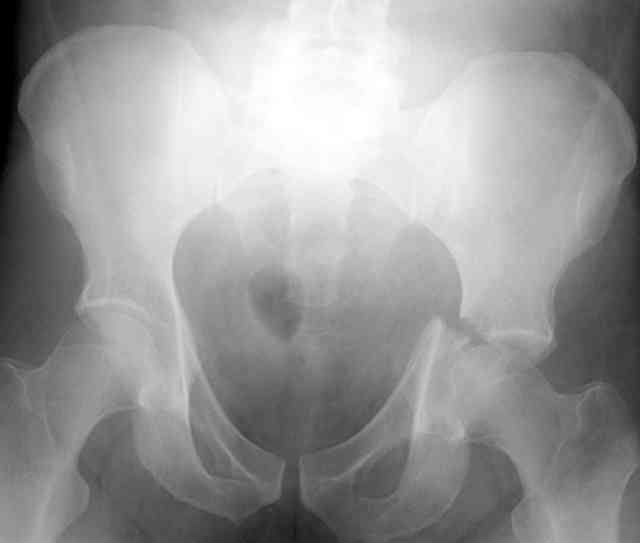

The 2nd example is of a motorcyclist with a transverse fracture-dislocation...he had a closed attempted reduction and placed in traction but the manipulative reduction was not concentric (not unusual for this injury pattern)...so the traction was adjusted to be just enough to disengage the head from the fracture (12#) until he could be cleared for surgery one day after injury...he was treated "urgently" then with a prone KL, clean the fracture, reduce and clamp it, screw it, support with a balanced plate, close, and enjoy...2-3hours, 400cc EBL, blah, blah, blah..